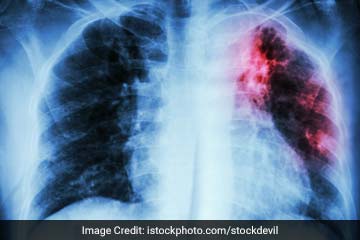

Tuberculosis (TB) is caused by bacteria (Mycobacterium tuberculosis) that most often affect the lungs. Tuberculosis is curable and preventable. TB is spread from person to person through the air. When people with lung TB cough, sneeze or spit, they propel the TB germs into the air. A person needs to inhale only a few of these germs to become infected. About one-third of the world's population has latent TB, which means people have been infected by TB bacteria but are not (yet) ill with the disease and cannot transmit the disease.